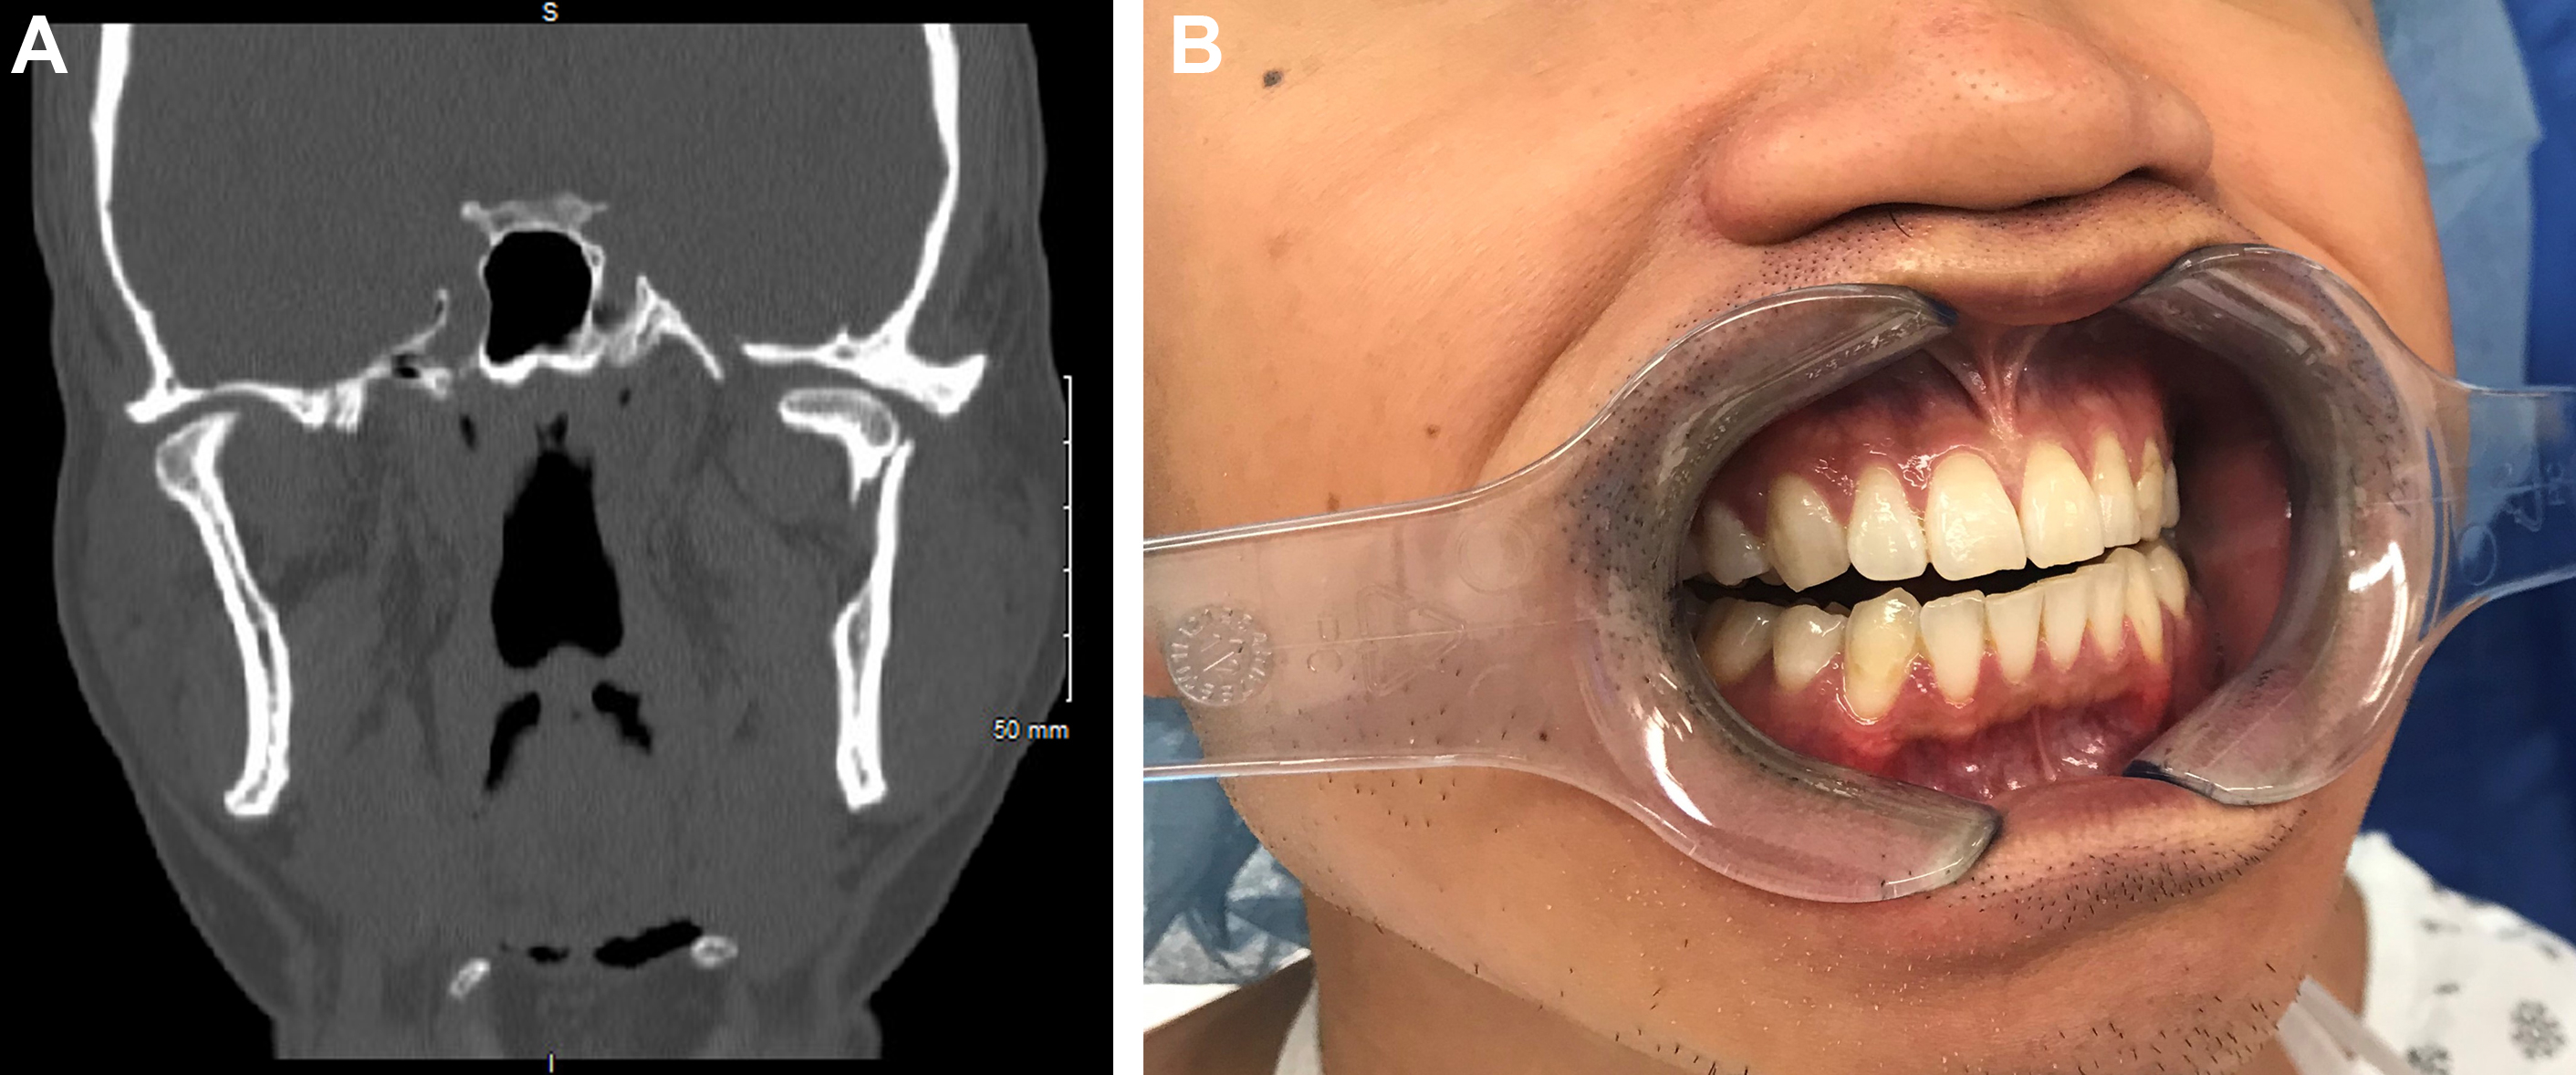

On examination, patients with condylar fractures may have tenderness and edema of the preauricular area; chin lacerations, ecchymosis, or edema; malocclusion, trismus, and deviation of the chin with opening. , Displaced unilateral condylar fractures can result in a loss of vertical ramus height, premature contact of the molar teeth on the injured side, and a posterior open bite on the contralateral side ( Fig. 5 ). The chin can deviate toward the side of injury during opening due to unopposed contralateral lateral pterygoid muscle contraction. Patients with bilateral condylar fractures have bilateral ramus height shortening and premature molar contact resulting in an anterior open bite malocclusion. Trismus, defined as a maximal incisal opening less than 40 mm, may be present due to functional interferences of the fracture segments, joint hemarthrosis, or pain. , Care must be taken in evaluating pediatric patients with a low threshold for imaging with CT scan—especially children presenting after a fall on the chin—to avoid missing a fracture.

Helical computed tomography is the gold standard for radiographic diagnosis and can be reconstructed into 3-dimensional images. The mandible series is a set of plain x-rays taken from 5 different views ( Fig. 6 ). Towne’s view (patient has their head angled downward 30°), lateral oblique, and lateral views are best for visualizing the condyle. Panoramic orthopantomogram may also be obtained and provides a single composite panoramic image.